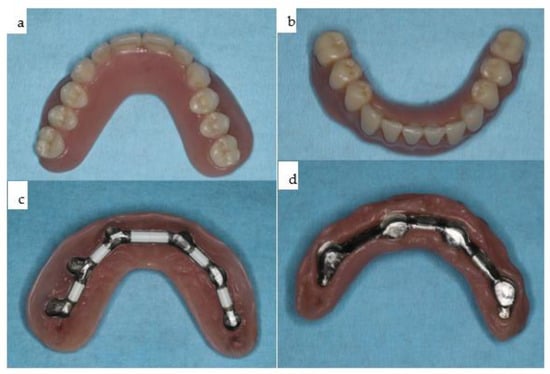

Six conventional dental implants were chosen for the maxilla to accommodate the interaction of chewing forces and the resulting biomechanical needs, given the mobile mandible reinforced with a primarily stable rigidly fixated subperiosteal implant, interacting with a non-mobile compromised maxilla. Primarily, there were no biomechanical limitations for loading the subperiosteal implant. However, due to the need for secondary stability in the maxilla for 3.5 months before placing healing abutments onto the six conventional implants, loading in the early phase was not a key issue. A bimaxillary final overdenture was planned, with a free hard palate in the maxilla and a non-precious bar retained as a final prosthesis in the mandible (Figure 23).

Figure 23. (ad): The two overdentures for the maxilla (a,c) and the mandible (b,d).